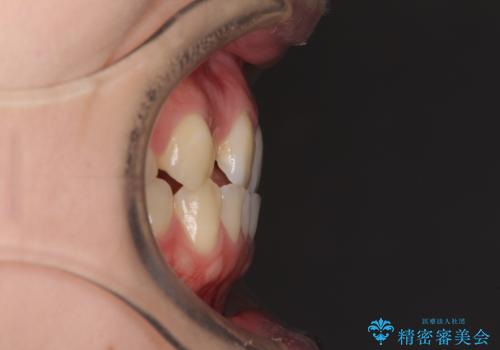

前歯のクロスバイトをインビザライン矯正で改善

- 前歯のデコボコと上下のクロスバイトを気にして来院された患者様です。

インビザラインを用い、IPR(歯と歯の間を削る)と歯列全体を拡大させることで、歯並びを整えていくこととしました。

上の前歯が下の前歯を乗り越える際、奥歯がほとんど咬めない時期があり、乗り越えた後も、インビザライン特有の奥歯の咬みにくさが続きました。

咬み合わせ改善のために治療期間を要しましたが、最終的に奥歯はしっかりと咬めるようになりました。